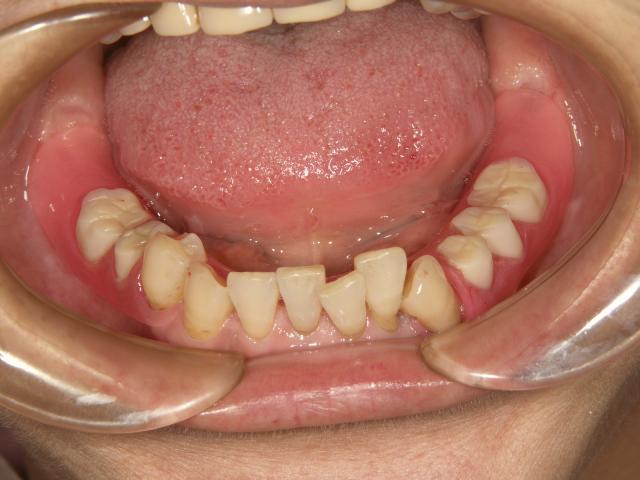

術前

ノンクラスプデンチャー

術後

ノンクラスプデンチャー ノンクラスプデンチャー ノンクラスプデンチャー

以前は金属のクラスプを使用した義歯使用していたが、今回ノンクラスプデンチャーに変更。

ややきつい感じがするが非常に軽くしっくりしているとの事!